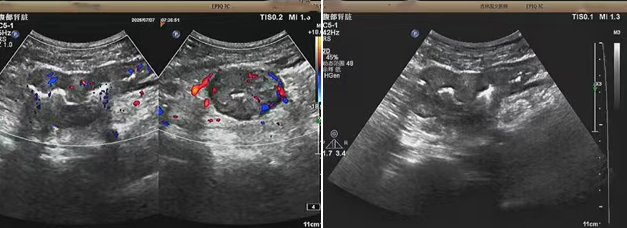

超聲檢查的結(jié)果進(jìn)一步揭示了病情的細(xì)節(jié):下腹部偏左腸壁顯著增厚,原本清晰的層次結(jié)構(gòu)遭到破壞,周圍脂肪間隙變得模糊,網(wǎng)膜回聲也出現(xiàn)增強(qiáng)的現(xiàn)象,同時(shí),腸腔狹窄的情況也得到了確認(rèn)。經(jīng)過完善的檢查,最終將病變精準(zhǔn)定位在乙狀結(jié)腸 - 直腸交界區(qū),并且對病變范圍及周圍浸潤情況做出了評估,這些關(guān)鍵信息為后續(xù)的診療工作提供了重要依據(jù),讓醫(yī)生們能更有針對性地制定治療方案。

我院超聲檢查在此次診療過程中展現(xiàn)出了顯著的技術(shù)亮點(diǎn)。一方面,它能做到 “明察秋毫”,通過高頻探頭可以清晰地顯示腸壁各層結(jié)構(gòu)的變化,為臨床判斷病變性質(zhì)提供了客觀、準(zhǔn)確的依據(jù),讓醫(yī)生能更清晰地了解腸道內(nèi)部的病變狀態(tài)。另一方面,它實(shí)現(xiàn)了 “精準(zhǔn)評估”,不僅準(zhǔn)確找到了病變的位置,還能全面評估病變對周圍組織的影響,這對于協(xié)助醫(yī)生制定科學(xué)合理的治療方案起到了至關(guān)重要的作用,有助于提高治療的有效性和安全性。